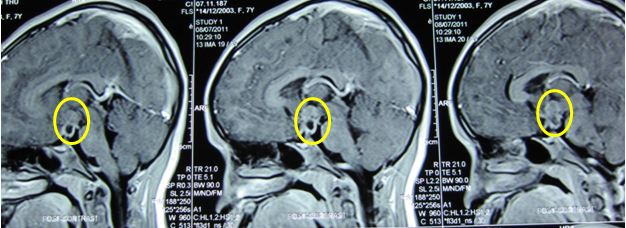

Hình ảnh Cộng hưởng từ (MRI) u vùng trên yên ngấm thuốc nhiều nghĩ tới Germinoma (u tế bào mầm tinh) (trước điểu trị)

Bệnh nhân được hội chẩn tại Trung tâm Y học hạt nhân và ung bướu-Bệnh viện Bạch Mai và được chẩn đoán là Germinoma (u tế bào mầm tinh)  trên yên thể khu trú đã gây suy yên, hướng điều trị là tia xạ gia tốc toàn não 1,8Gy/ngày x 3 buổi, sau đó đánh giá lại bằng cộng hưởng từ và xét nghiệm xét điều trị tiếp sau.